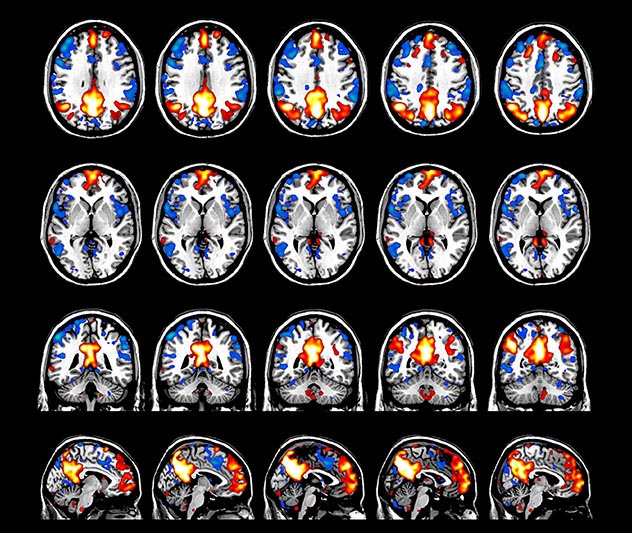

BOLD fMRI activation, depicted in color, of left anterior insula (MNI plane z = 8 mm) in a single subject by a contrast between viewing and matching faces with negative emotion (angry, sad, scared) versus happy faces. The voxelwise threshold is p < 0.001, and colored voxels survive false discovery rate correction to p < 0.05. The activated voxels in color are overlaid on the subject's own 3D-TFE image displayed in grayscale, after transforming the data to MNI space. The fMRI pulse sequence was a single shot FFE echo planar acquisition using MultiBand SENSE factor 6, dS SENSE factor 1, isotropic voxel size 2.4 mm, 60 transverse slices, TR 950 ms, TE 30 ms, flip angle 52 degrees, 517 dynamic scans, total scan duration 8:21 minutes. Image provided by James M. Bjork, PhD, Associate Professor of Psychiatry at VCU.

The fMRI pulse sequence was a single shot FFE echo planar acquisition using MultiBand SENSE factor 5, dS SENSE factor 1.25, isotropic voxel size 2.7 mm, 50 transverse slices, TR 700 ms, TE 30 ms, flip angle 52 degrees, 765 dynamic scans, total scan duration 9:01 minutes. Image provided by Matthan Caan, PhD, Assistant Professor at the AMC.

Imaging was performed using Ingenia 3T CX with a 32ch dS Head coil, TR 1.6 sec, TE 35 ms, voxel size 3.1 x 3.1 x 3.1 mm, 46 slices and Multiband SENSE factor 2. Image provided by Dr. Gispert

Default mode network as discovered by resting state fMRI in one participant of the ALFA cohort [7]. rs-fMRI allows us to find networks of brain regions with highly correlated activity and sustaining distinct brain functions. The default mode network (in warm color scale) is active when the brain is focused on introspective thinking and has been shown to be altered in Alzheimer’s. Interestingly, brain areas of this network are known to show abnormal levels of one of the pathological hallmarks of Alzheimer’s (b-amyloid deposition) in preclinical stages. We want to better understand the alterations of these brain networks in preclinical stages of Alzheimer's and explore their potential use as biomarkers.